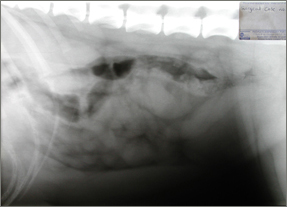

Radiography

The following morning the dog was sedated with 0.6 mg acepromazine (ACP, C VET) and 0.3 mg buphrenorphine (Temgesic, Schering Plough) by intramuscular route and a right lateral radiograph of the abdomen was taken under sedation. The radiograph confirmed the diagnosis of a pyometra. See radiograph 1 right.